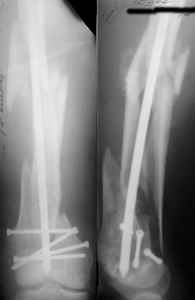

I presented a series of ~25 such cases at EuroTrauma'2004. Many cases were discussed here. I attach am example. Look also recent cases at http://www.hwbf.org/hwb/conf/alex58/scfx.htm,

I do realize that you are master surgeon, and congratulations on another excellent, spectacular case (result), but,

- Your last posted case: how is possible to have secure fixation with applied construct without additional casting, bracing or Ilizarov?

At that moment we had in stock only the 10 mm solid nails so of course there was no idea about early weight bearing. But it was quite enough for early knee ROM excersises (see attached). Two locking screws through the distal block provided that.

Of course if we talk about antegrade nailing in distal femoral fractures with the particular technique even better than 70% results can be achieved - after appropriate learning curve, not so long.